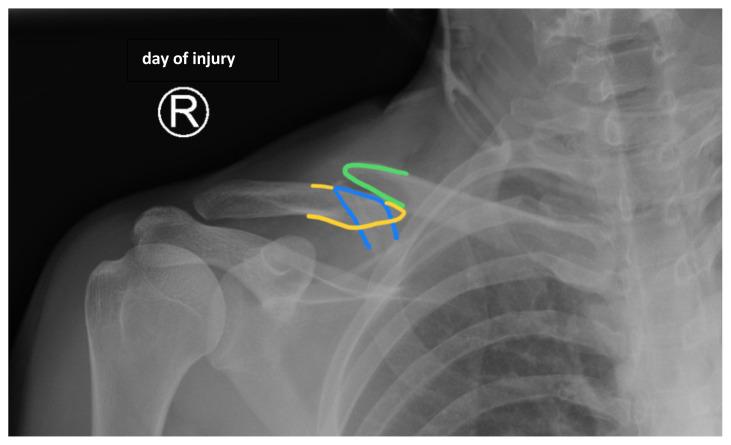

成人锁骨骨折病例报告。

Adult Clavicular Fracture Case Report.

Clavicular fractures make up 2-4% of all fractures. While most are nondisplaced and easily managed, serious complications can arise from more severe fractures. In these cases, immediate surgical intervention is required. However, there lacks a consensus regarding the optimal treatment for fractures that are less severe. Here, we present a case of a 25-year-old male with a comminuted displaced mid-clavicular fracture. This report details the important clinical features of various types of clavicular fractures and discusses the current literature regarding indications for operative and nonoperative management.

锁骨骨折占所有骨折的2% - 4%。虽然大多数骨折无移位且易于处理,但较严重的骨折可能会引发严重并发症。在这些情况下,需要立即进行手术干预。然而,对于不太严重的骨折,目前尚无关于最佳治疗方法的共识。在此,我们报告一例25岁男性的粉碎性移位锁骨中段骨折病例。本报告详细介绍了各类锁骨骨折的重要临床特征,并讨论了当前有关手术和非手术治疗指征的文献。